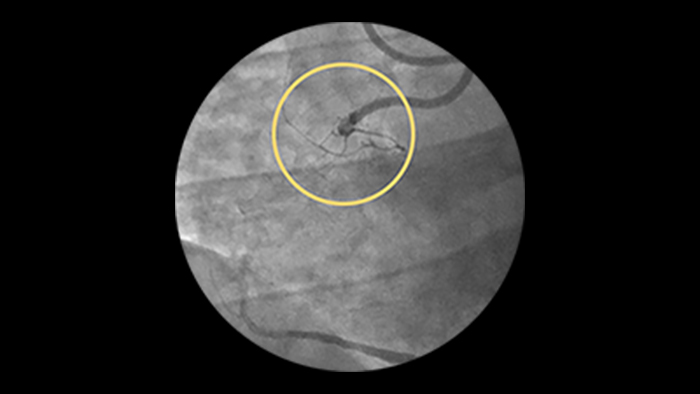

Chronic total occlusions

Incidence increases with age, yet older patients are less likely to have PCI attempted.5